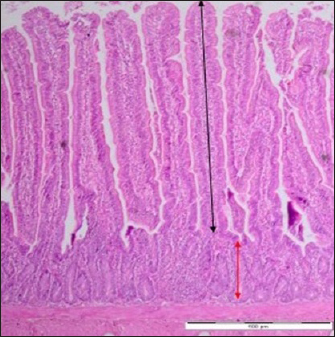

The intestinal segments from the duodenum, jejunum, and ileum samples were processed and stained with hematoxylin and eosin (HE). The tissues were examined under light microscopy (Motic BA410) connected with a camera (Motic Moticam pro 285A) for determination of the villi height and crypt depth using the software of motic images plus 2.0 ML. The villi heights and the crypt depths were measured from the tip to the crypt junction and from the base to the villi junction, respectively (Gava et al., 2015) (Fig. 1). Three readings were recorded for every collected sample.

Fig. 1. Villi height and crypt depth of the intestine of SPF chick. Black arrow (villi height) extending along the villi of the duodenum. Red arrow (crypt depth) extending from the base to the villi junction. Control group. Day 7 pi. HE staining. Bar=4 μm (40×).